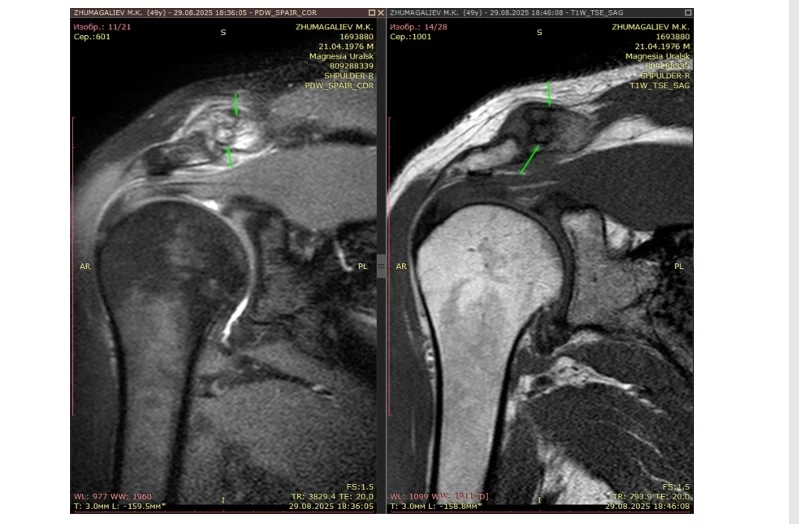

Былтыр 25 қарашада Малик Жұмағалиев Астанадағы академик Н.Д.Батпенов атындағы Травматология және ортопедия ұлттық ғылыми орталығында дәрігер қабылдауында болған. Сол жерде мамандар оған "оң жақ иық буынындағы импиджмент-синдром" деген диагноз қойған. Яғни иықтағы сіңір мен сүйек бір-біріне үйкеліп, ауырсыну туғызатын жағдай.

Осыдан кейін ол қайтадан дәрігерге қаралып, МРТ-ға жолдама алған. Нәтижесі бойынша оған "иық буынының импиджмент синдромы" немесе "тендинит" болуы мүмкін екені айтылған. Малик бұл диагнозды толық медициналық тілде түсіндіріп беретін маман болмағанымен, өз бетімен зерттеп, жағдайдың неден екенін шамалаған.

"МРТ-ға жібергеннен кейін таныстарымның бірі “иық буынының импиджмент синдромы” болуы мүмкін деді. Кейде оны тендинит деп те атайды екен. Сол кезде сіңір қабынып, кейде жартылай жыртылып, бұлшықет те ішінара зақымданады дейді. Дәрігер емеспін, бірақ өзімше түсініп алдым. Сіңір ротаторлық манжетамен үйкеліп, сүйекке тиіп тұрады. Сол үйкелістен қатты ауырады. Сондықтан қозғалысты барынша азайту керек болды. Бәрін дұрыс істеп, қолды көп қимылдатпауға тырыстым", – дейді ер адам.

Кейін ол операция Астанадағы Бәтпенов атындағы Ұлттық ғылыми орталықта жасалатынын білген. Осы себепті Малик ақылы онлайн қабылдауға жазылып, МРТ қорытындысын жіберген. Онлайн консультацияда бөлім меңгерушісі оның жағдайын қарап, иықтағы сіңірдің жыртылғанын нақты растаған.

"Орталыққа МРТ қорытындысын жүктеп жібердім, жарты сағаттай кеңес өтті. Маған бәрін егжей-тегжейлі түсіндірді, сұрағым да қалмады. Бөлім меңгерушісі өзі қарап, нақты айтты. Сіңір жыртылған, үзіліп кеткен, сондықтан операция керек деді. Операция күрделі емес, жалпы наркозбен жасалатынын айтты. Кейін екі айдай уақыт оңалтудан өтемін, сосын біртіндеп қалпыма келіп, қайта жаттығуға көшуім мүмкін екенін жеткізді", – дейді Малик.